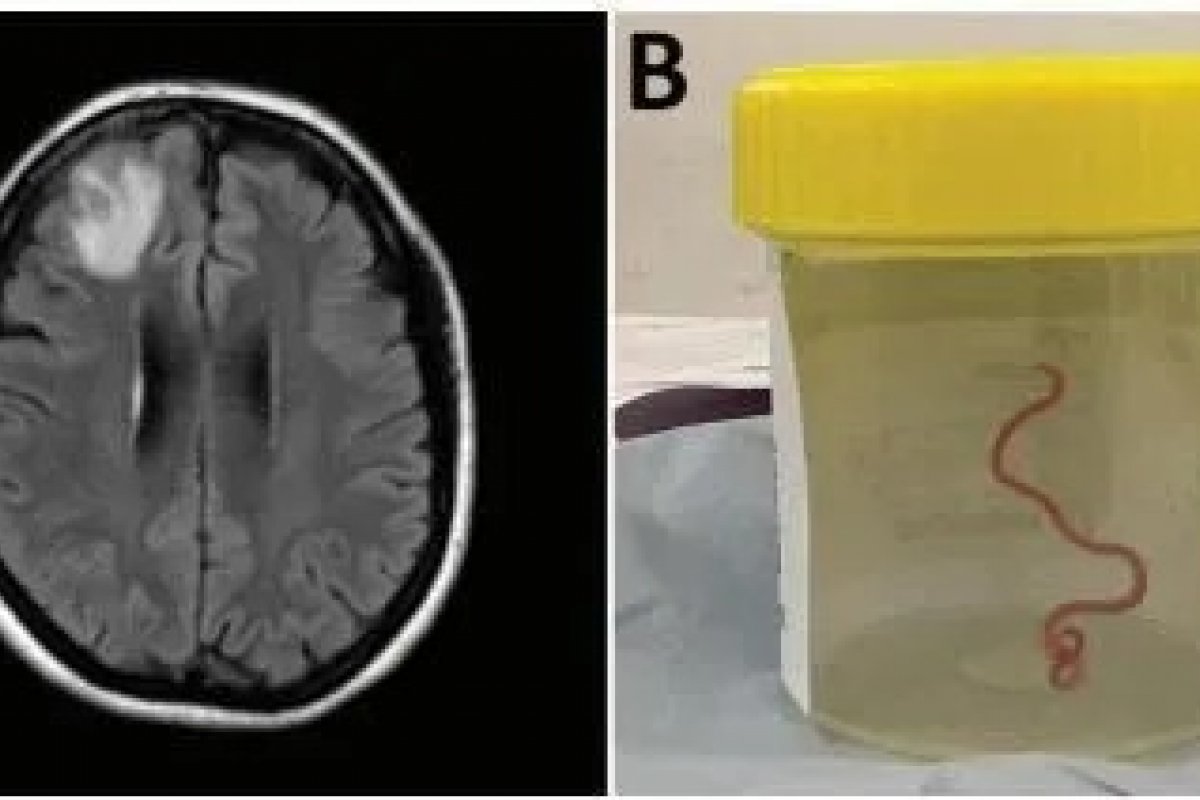

Um verme de 8 centímetros, que é considerado um parasita comum em cobras píton, foi descoberto no cérebro de uma mulher de 64 anos em Nova Gales do Sul, na Austrália. Este caso é apontado como o primeiro a ser registrado no mundo, conforme relatado em um artigo publicado na revista científica "Emerging Infectious Diseases".

Em 2022, a paciente buscou novamente o serviço de saúde relatando piora da depressão e perda de memória. Ao realizar uma ressonância magnética foi constatada uma lesão no lobo frontal direito, exigindo uma biópsia. Durante o procedimento, os médicos viram que, na verdade, a lesão se tratava de um parasita vivendo dentro do cérebro. A cirurgia de retirada do verme ocorreu em junho de 2022 e o caso foi divulgado na edição de setembro da revista científica.